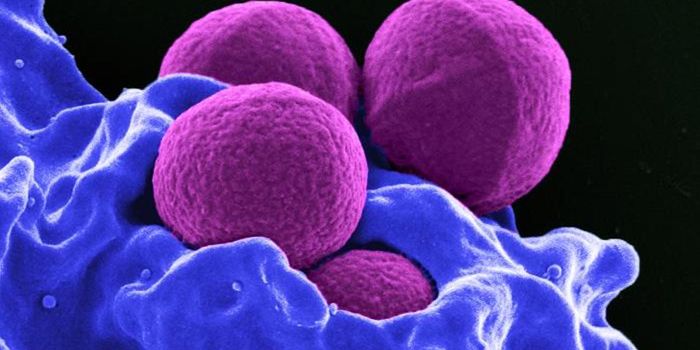

SEP 17, 2021Cell & Molecular BiologyMRSA (methicillin-resistant Staphylococcus aureus) is a well known superbug, a pathogenic microbe that can cause serious ...